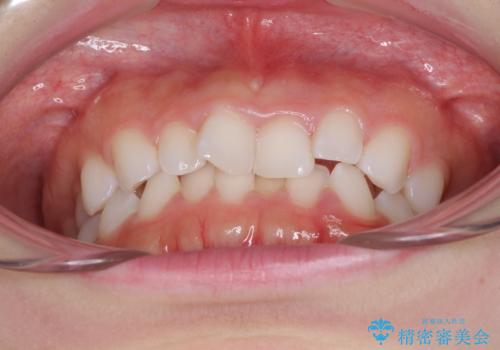

デコボコと深い咬み合わせの改善 インビザラインによる矯正治療

- 口元のデコボコと深い咬み合わせ(ディープバイト)を気にして来院された患者様です。

インビザラインによる上下歯列の拡大と、IPR(歯と歯の間を削る)にるスペースの獲得により、口元のデコボコとディープバイトを改善することとしました。